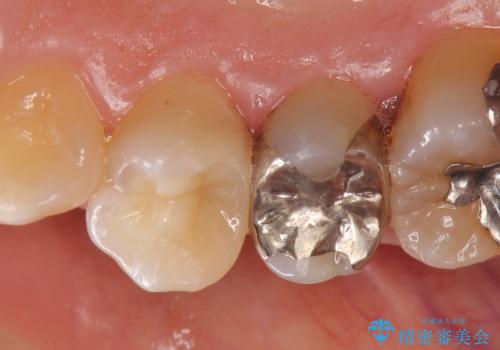

- 右上4番目の歯がしみるといらっしゃった方の症例です。

古い樹脂を除去後、セラミックインレーによる修復を行いました。

当院のセラミックインレーはemaxという強度と審美性に優れた材料を使用しています。

またプレス方式でインレーを製作しているため、削り出しで製作するCADCAMより優れた適合性も持ち合わせており、虫歯が再発しにくい修復物です。